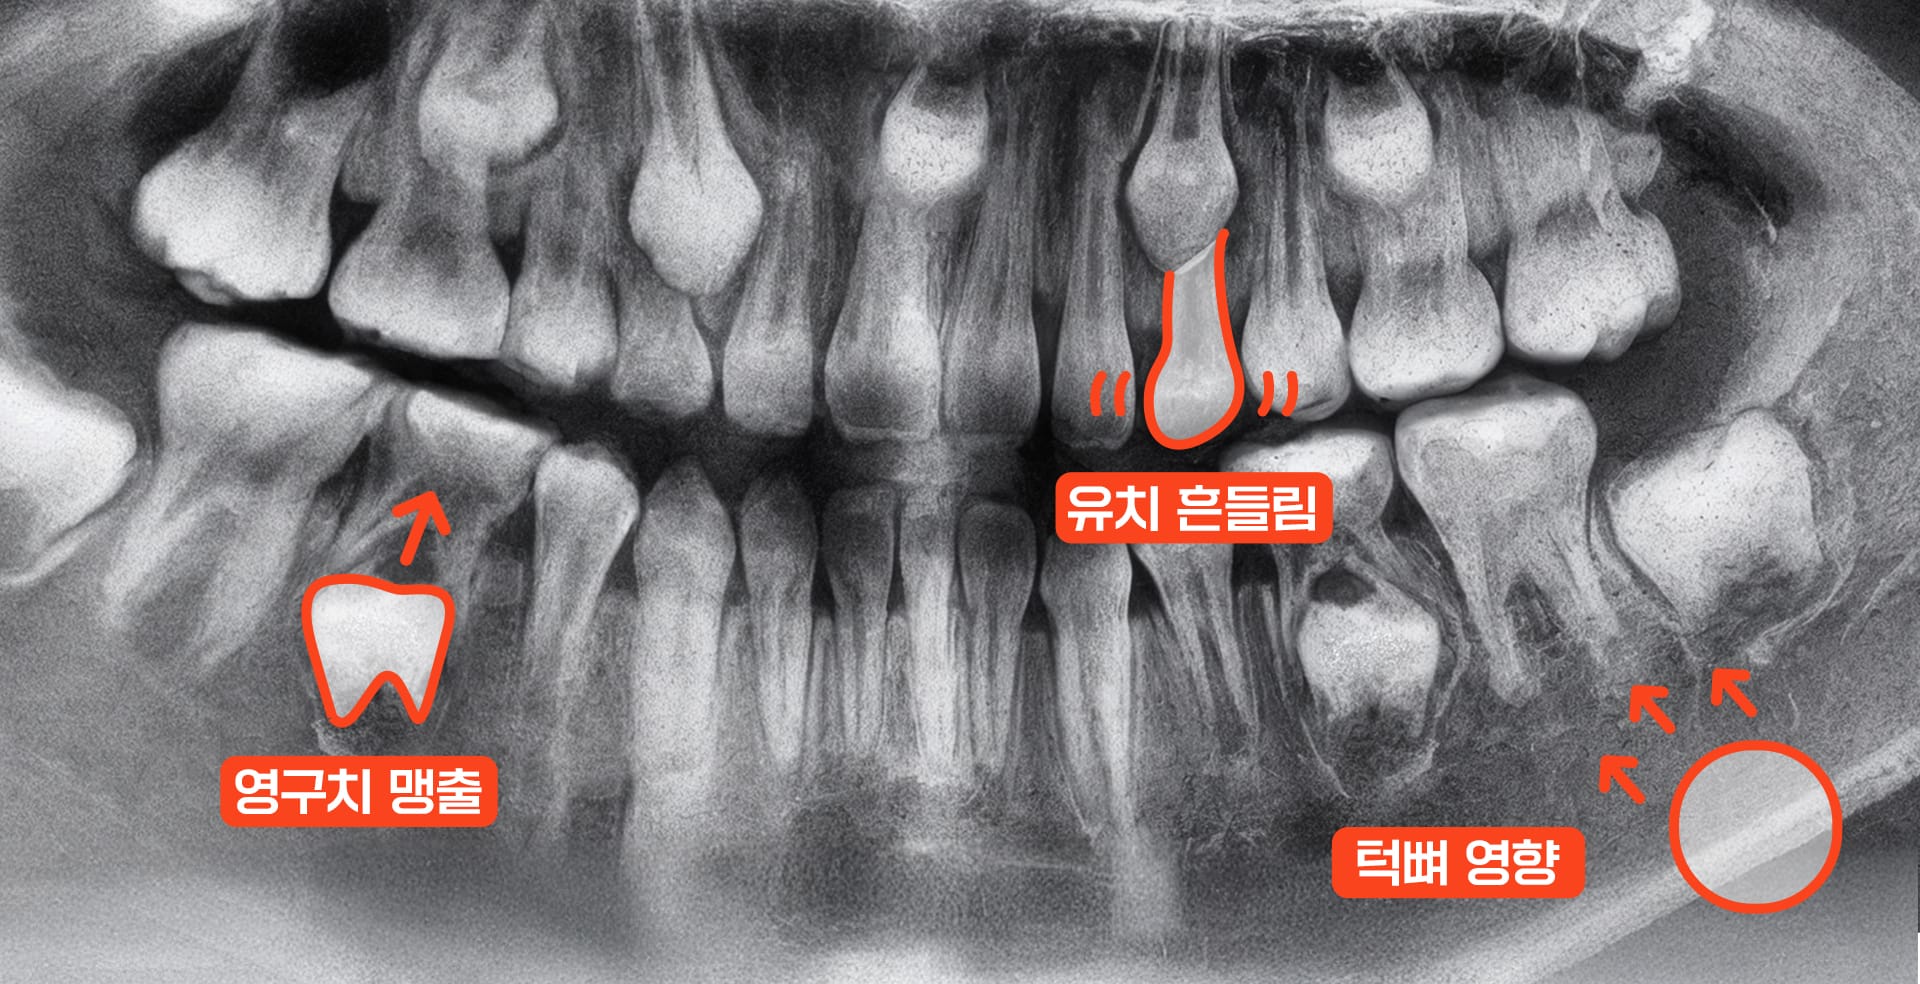

아이의 성장기, 특히 초등학교 시기(만 6~12세)는 턱뼈가 유연하게 자라는 치아교정 골든타임입니다.

이때는 교정 장치나 습관 교정만으로도 턱 성장 방향을 바로잡아 부정교합 원인을 줄일 수 있어, 발치나 수술 가능성도 낮아집니다.

첫 영구치가 나는 만 6~7세경에 첫 검진을 받는 것이 좋습니다. 이상 신호가 없더라도 이 시기에 턱과 치아의 성장 상태를 미리 확인하면 적절한 교정 시기를 놓치지 않을 수 있습니다.